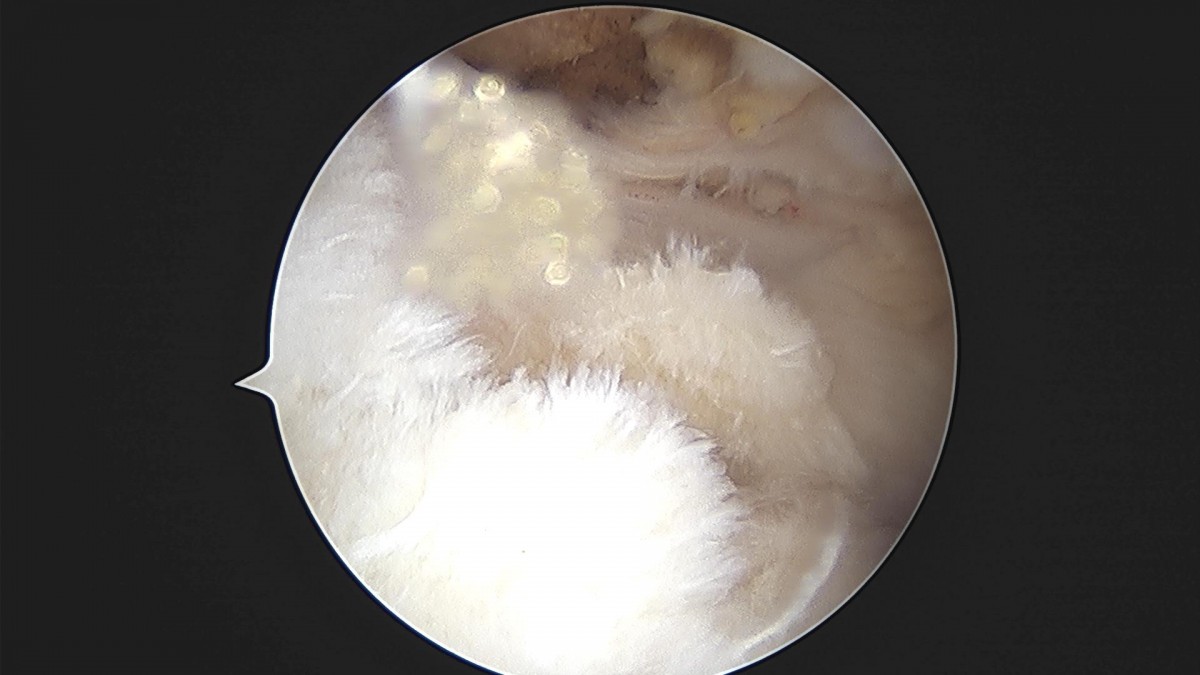

최원락 원장님 어깨 회전근개 봉합술 김O 환자

f537707b0b9f2537509492404de31ecf_1716863776_082.jpg